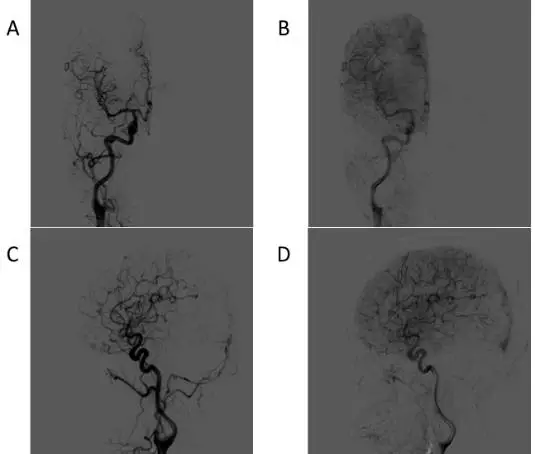

入院后进一步行DSA检查,提示左侧横窦区硬脑膜动静脉瘘,由双侧颈外动脉参与供血(分别为左侧脑膜中动脉和右侧耳后动脉及枕动脉多个分支),通过皮层静脉向上矢状窦后份引流,椎动脉系统不参与供血(图2、3、4)。

图2. 术前右侧颈总动脉造影提示:A/C动脉早期可见左侧硬脑膜动静脉瘘瘘口,右侧耳后动脉及枕动脉分支参与供血,动脉早期可见提早显影的引流静脉。B/D 动脉晚期可见硬脑膜动静脉瘘藉皮层静脉向上矢状窦引流。

图3. 术前左侧颈总动脉造影提示:A/C动脉早期可见左侧硬脑膜动静脉瘘瘘口,左侧脑膜中动脉多个分支参与供血,动脉早期可见提早显影的引流静脉。B/D 动脉晚期可见硬脑膜动静脉瘘藉扩张的皮层静脉向上矢状窦引流。